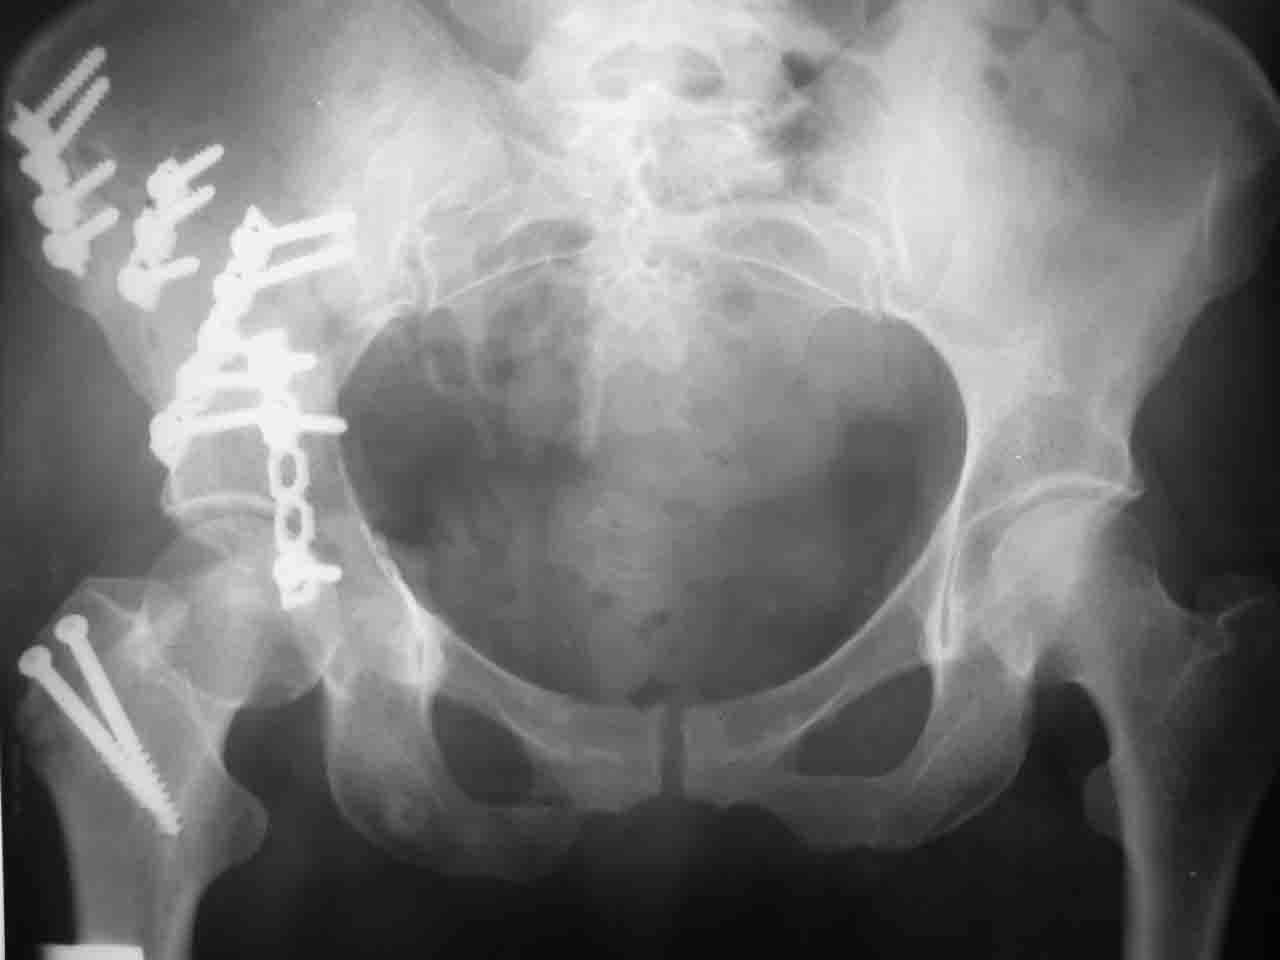

Спасибо за комментарии и рекомендации. Откровенно говоря, больного я прооперировал на прошлой неделе, через 5 дней после аварии и проблем с ним пока никаких нет, на удивление при достаточно обширной диссекции (илиофеморальный доступ) болей практически нет, так что больной самостоятельно садится в кровати, выполняет активные движения в оперированном суставе, сгибая до 60 градусов пока, далее с ассистенцией.

Причиной обращения к сообществу были возникшие непосредственно после операции сомнения и разочарования полученным качеством репозиции: а надо ли было трогать перелом вообще, репозиция передней колонны технически была очень сложна для меня, хотя реконструкции была в той же последовательности, что Д-р А.В.Рунков рекомендовал, в какой-то момент безуспешных манипуляций стал думать о *вторичной конгруэнтности*, которую не так давно обсуждали на

форуме и скелетном вытяжении. С репозицией и фиксацией задней колонны и отдельно задне-верхней стенки впадины проблем не возникло. Послеоп. Рг граммы в приложении. Если возникнут какие-либо дополнения или поправки - был бы признателен.